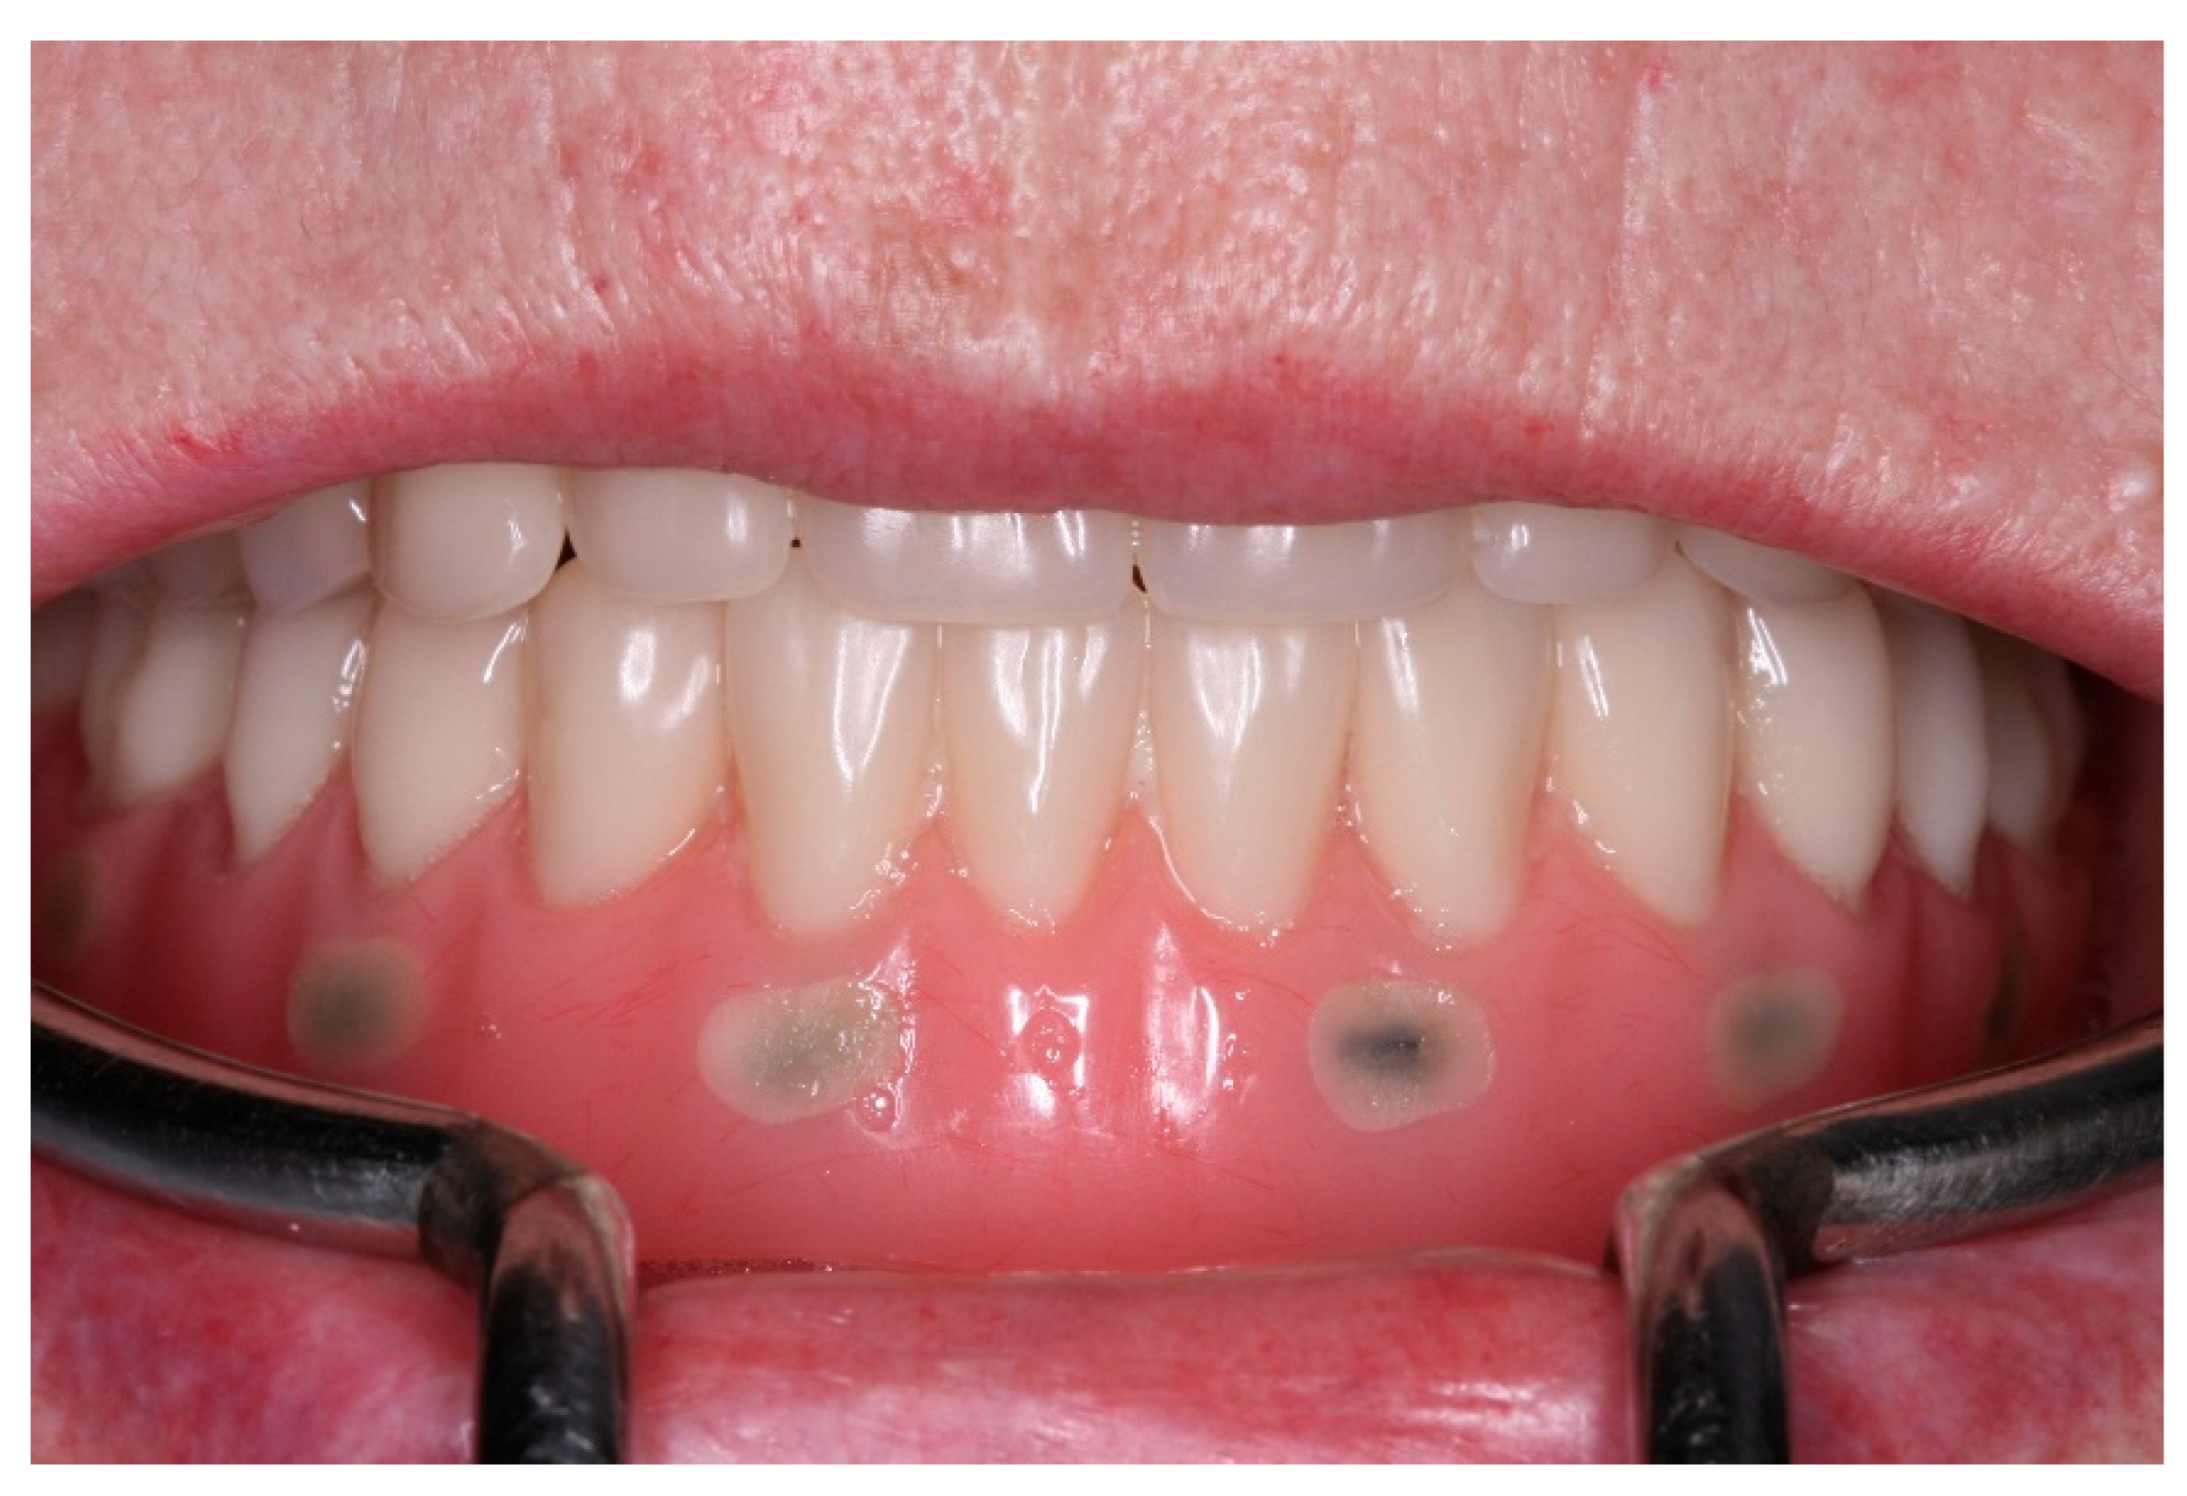

After a healing period of 3 months the patient returned to change que temporary fixed prothesis for a new one, more delicate and with a reinforced metallic bar for a better ferulization of the implants and better dissipation of the stress during function. After removal of the temporary prosthesis we could see the peri-implant mucosa was healthy (Figure 19), without bleeding on probe nor peri-implant sulcus with more than 3mm depth, even around the implants were there were lack of a satisfactory keratinized tissue band, showing us that the patient was being able to maintain the cleansing of the region below the prosthesis. A new fixed rehabilitation over the implants was produced (Figure 20, Figure 21 and Figure 22). 2 years after the surgery we could see on a control panoramic radiograph no signs of bone remodeling above the expected around the implants (Figure 23).

Figure 21. Buccal view of the new fixed screw-retained full-arch rehabilitation in occlusion.